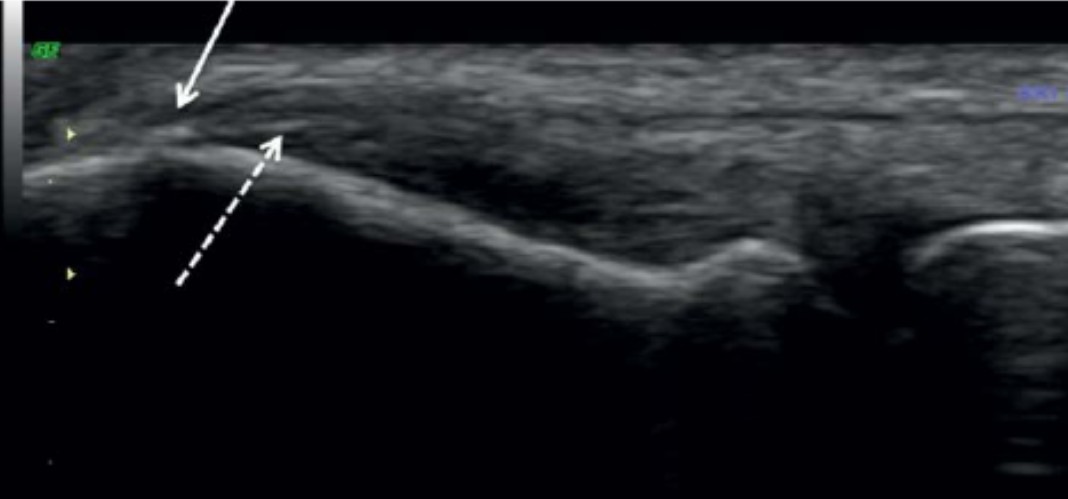

En la imagen ecográfica se observan cambios degenerativos iniciales en la inserción del tendón extensor común.

La flecha continua (la más alta) señala una irregularidad en la zona de unión entre el ligamento, el tendón y el hueso. Esta irregularidad se relaciona con pequeños cambios cálcicos en la entesis, todavía sin formar un entesofito claro.

La flecha discontinua (la más baja) marca una pequeña cicatriz o zona de alteración en la parte profunda de la inserción. Es un cambio sutil que muestra una degeneración iniciándose en la zona profunda del tendón.